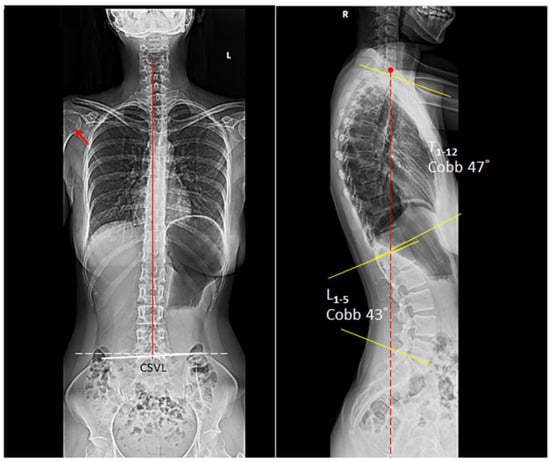

The patient was treated with cervical adjustment and soft tissue massage (STRIG Massage Device, Seoul, Korea) three times per week with emphasis on restoring mobility to stiff joints and relieving muscle tightness [,,]. At the end of first month, the patient reported that her neck and upper back pain was fully recovered. She also stopped all medications as her symptoms of heartburn had concurrently eliminated. A rehabilitation program including tuck chin exercises and lifestyle modification was added to the second phase of treatment plan to strengthen the muscles [,,,]. The patient continued to receive chiropractic adjustment twice per month for correcting spinal alignment. Restoration of the posture was demonstrable on the full spine radiographs at 9 months follow-up (Figure 2). At 12 months after initiating treatment, the patient remained healthy, free of pain and GERD, in the pandemic home-office.

Figure 2.

At 9 months follow-up, the thoracic kyphotic angle reduced to 47° and the GERD also resolved. The patient remained pain- and GERD-free at the 12-month follow-up visit. In a balanced state, the C7 plumb line (dashed red line) should fall within 3 cm, either anterior or posterior, of the posterosuperior corner of the S1 endplate.